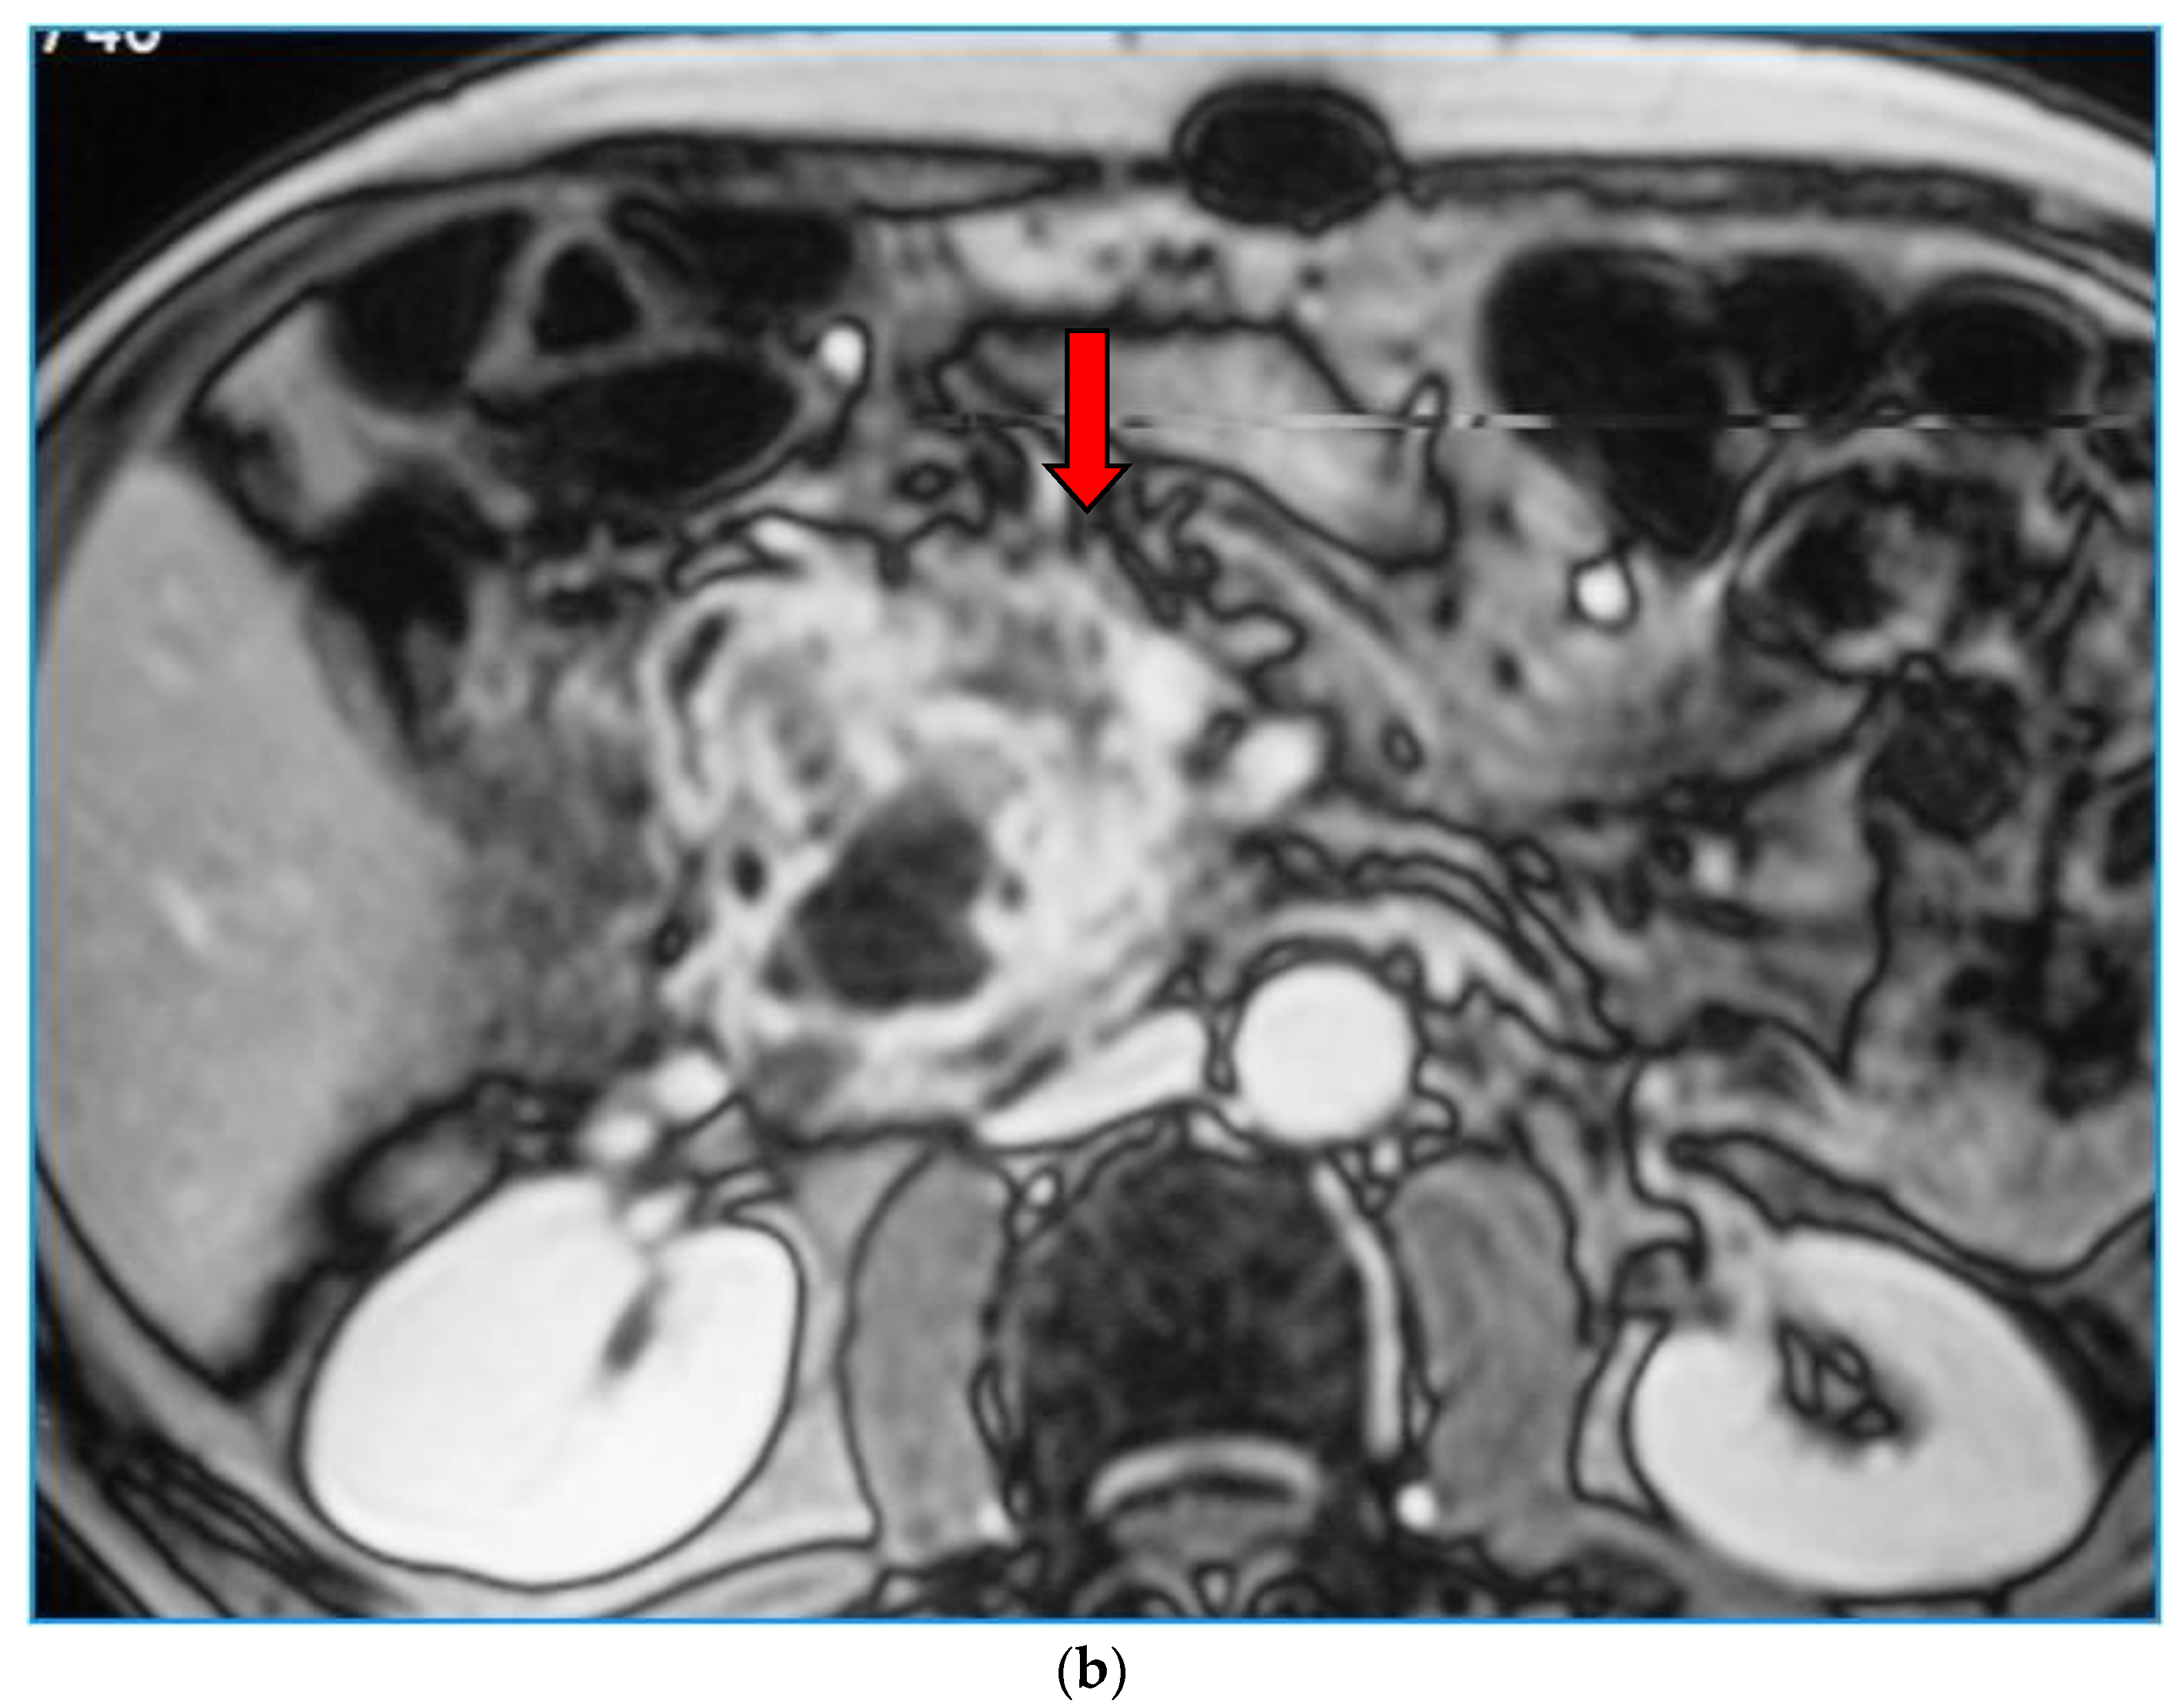

2. Imaging Findings

3. IPMN-Related Complications